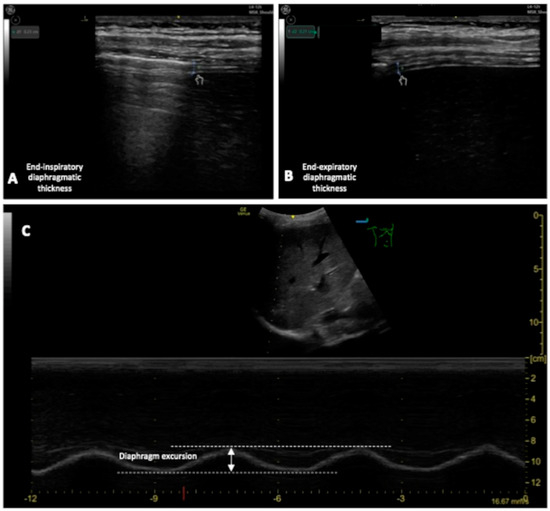

4.2.4. Diaphragm Ultra-Sound (DUS)

- Diaphragm thickening fraction (DTF), measurement of the difference in end-inspiratory and end-expiratory diaphragmatic thickness, expressed as a fraction;